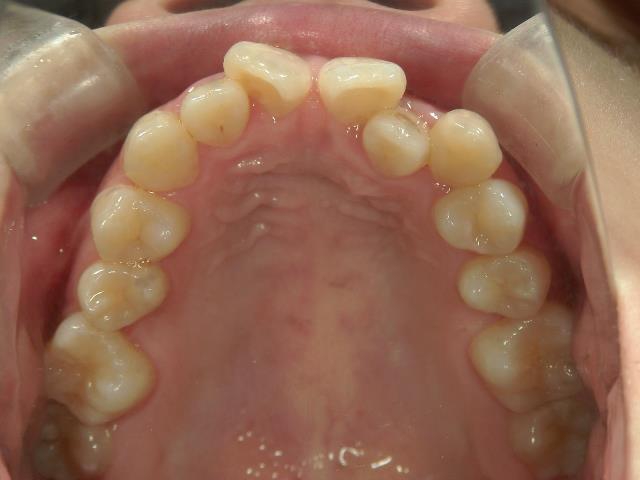

矯正歯科 治療前

矯正_灰色.pngno.8_8495_治療前_上.jpg矯正_灰色.png

no.8_8495_治療前_左.jpgno.8_8495_治療前_正面.jpgno.8_8495_治療前_右.jpg

矯正_灰色.pngno.8_8495_治療前_下.jpg矯正_灰色.png